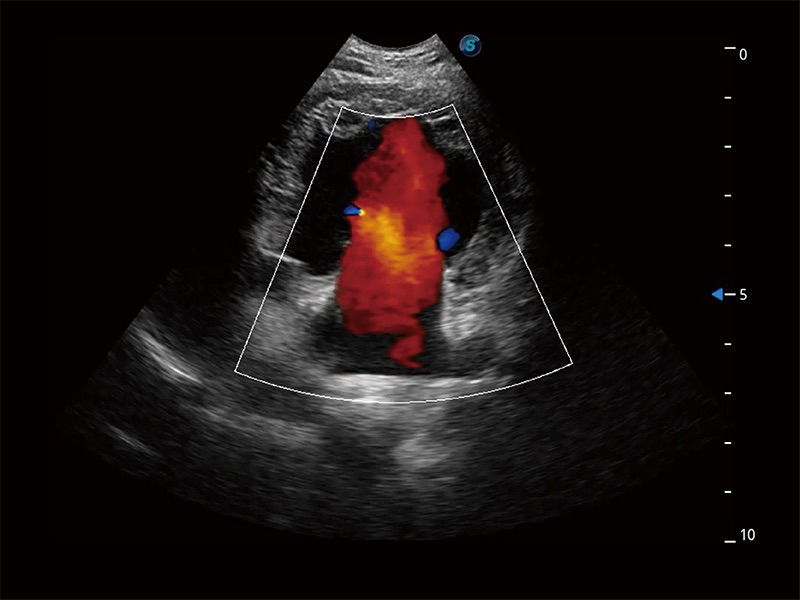

非线性融合造影成像充分利用谐波和基波信号,为难以观察的血流进行增强显像。可用于线阵、凸阵、微凸阵、相控阵探头。

在传统二维血流成像的基础上,呈现血流的立体感,具有动感的生命力之美。即便是微小的血管也能轻松应对,提高了血流的视觉敏感性。